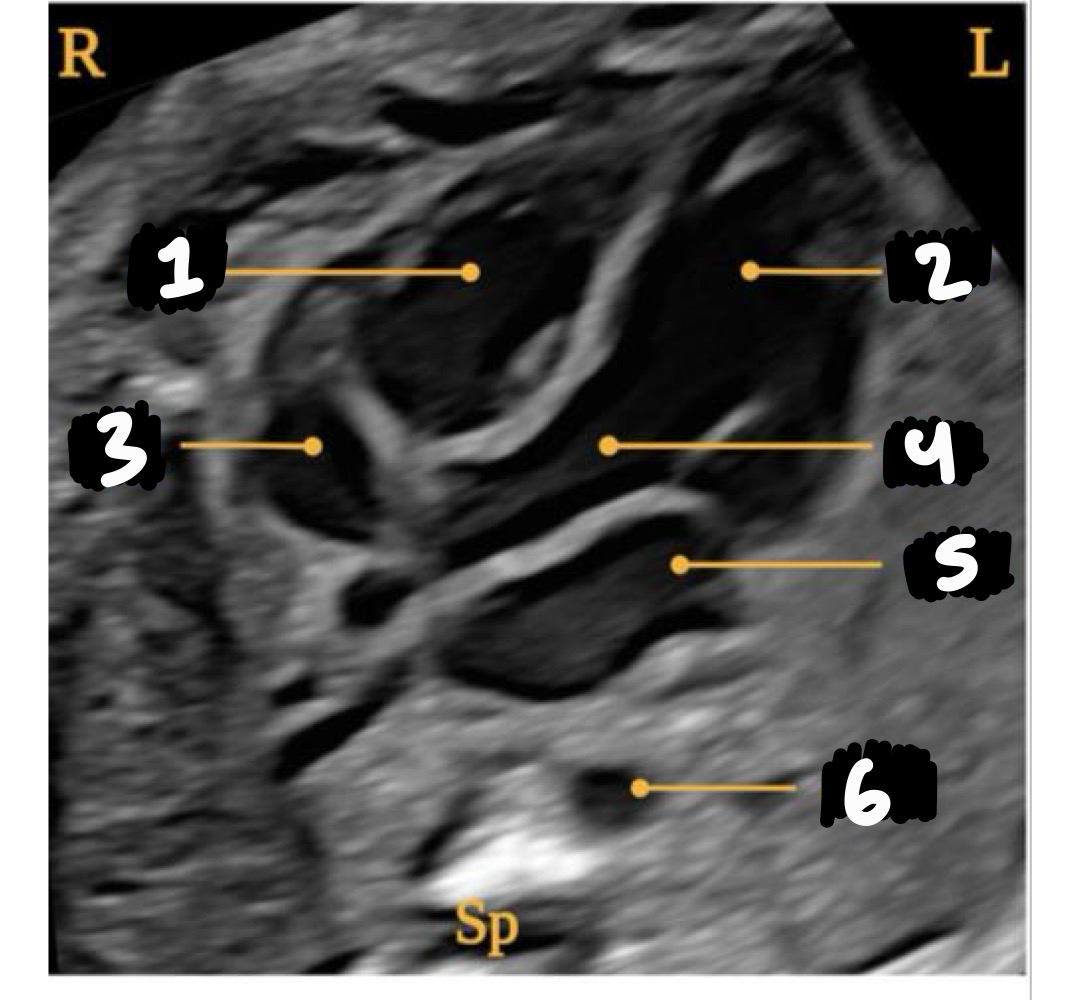

Right ventricle

Left ventricle

Right atrium

Aorta

Left atrium

Descending aorta